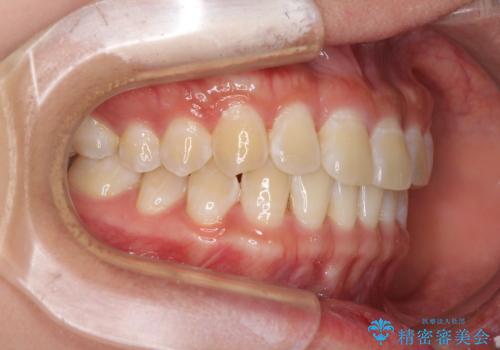

前歯の隙間と上下正中のズレを解消

- 上下前歯隙間と正中のズレを改善したいとのことで来院された患者様です。

自己管理を減らしたいとのことで、ワイヤー装置による矯正治療を行うこととしました。

正中がなかなか合わずに、2年近くの治療期間を要しました。